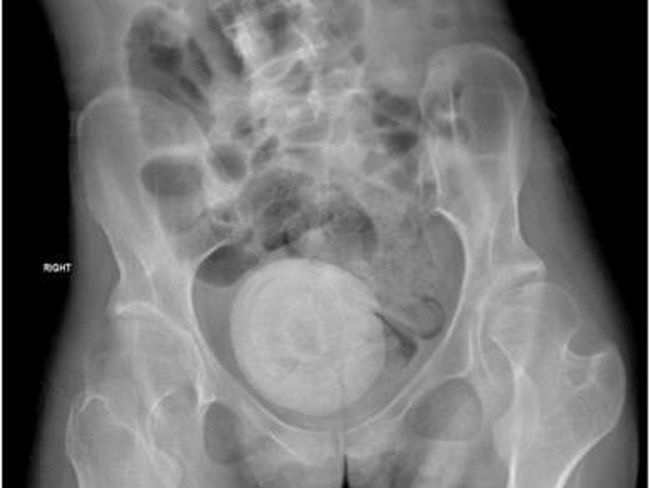

Batu vagina di antara organ panggul (Foto: Sciencedirrect)

Ia kemudian menjalani pemeriksaan ginekologi dan dokter memastikan ada 'batu' seukuran jeruk besar di antara organ panggulnya.

Setelah dipecah menjadi beberapa bagian, batu-batu tersebut dikeluarkan menggunakan tang saat operasi yang berlangsung selama tiga jam. Batu vagina yang bersarang di antara organ panggul wanita tersebut sangat besar sehingga menekan kandung kemihnya. Kondisi ini mengurangi kapasitas dan menyebabkan kebocoran urine.

Setelah dioperasi, pasien kemudian dipulangkan dengan antibiotik, dan perawat disarankan untuk melakukan tindak lanjut yang dijadwalkan. Analisis batu yang ada di antara organ panggul wanita tersebut terbentuk dari campuran kalsium oksalat dan kristal struvite.

Di samping itu, dokter menjelaskan batu vagina seperti dialami wanita tersebut adalah kasus yang jarang. Mirip dengan batu ginjal, batu vagina biasanya dipengaruhi oleh berbagai faktor termasuk pola makan, pH urine, stasis urine, microbioma, hormon seks, dan genetik.